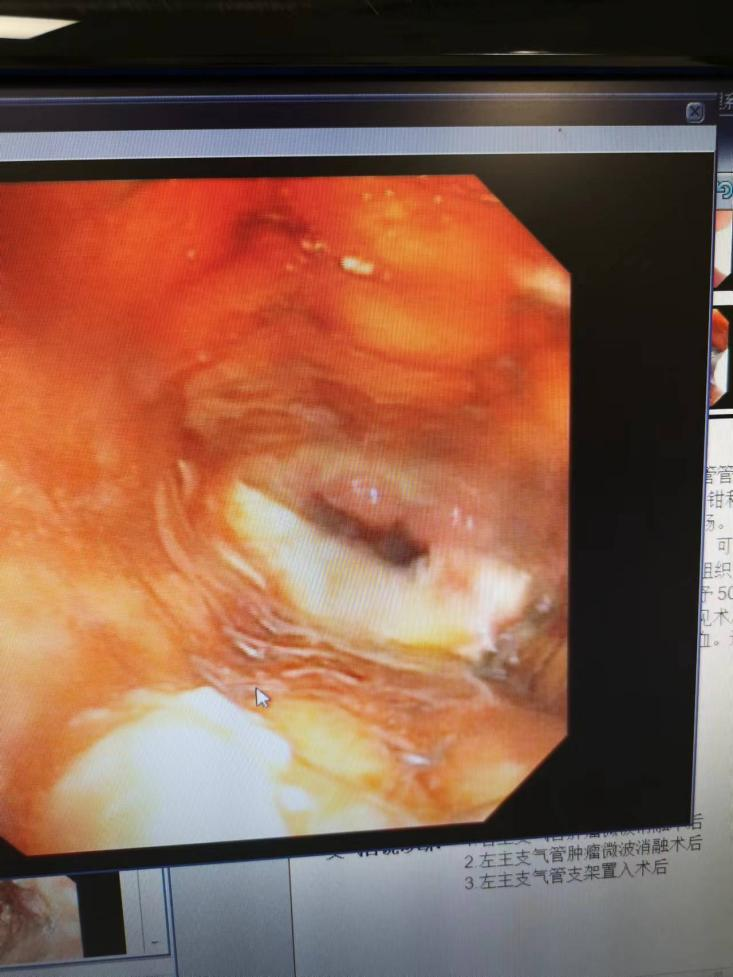

Treating Esophageal Tumor + Airway Compression Obstruction with Endoscopic Microwave Ablation + Biol -